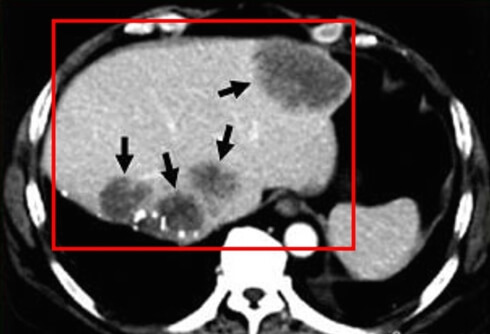

오늘은 전반적인 간암의 치료방법과 수술, 그리고 간암 수술 후 재발 가능성에 대해서 설명을 드리도록 하겠습니다.

간암 역시 초기에 발견하여 절제 수술을 하거나, 간 이식이 가능한 경우에는 어느 정도 완치 가능성을 보이지만 시기를 놓칠 경우 사망률이 급격하게 올라가는 암입니다.

환자 각 개인마다 가지고 있는 암의 성질과 형태, 그리고 크기와 위치 등의 요인으로 인하여 치료방법이 다양하게 나누어지게 됩니다.

그리고 간암의 경우 환자의 간 기능에 따라서 치료법이 많이 달라지게 됩니다. 즉, 간 기능이 얼마나 좋고, 유지되냐에 따라서 암 치료법이 여러 방법으로 나누어진다고 볼 수 있습니다.